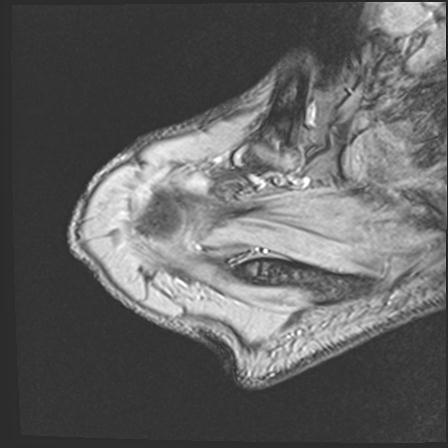

60058 3/9 11/4 右肩 2R+MRI 73歳男性 肩腱板損傷